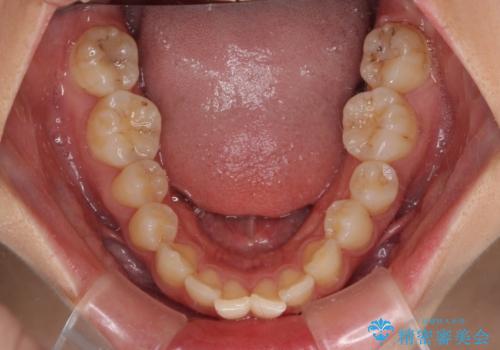

左右ともに奥歯の咬み合わせが上顎前突となっており、上顎前歯が飛び出している状態でした。

奥歯の咬み合わせ改善が必要であるため、マウスピース矯正より確実に達成のできるワイヤー矯正にて治療を行うこととしました。

奥歯の咬み合わせはしっかりと改善され、前歯の突出感も改善されました。